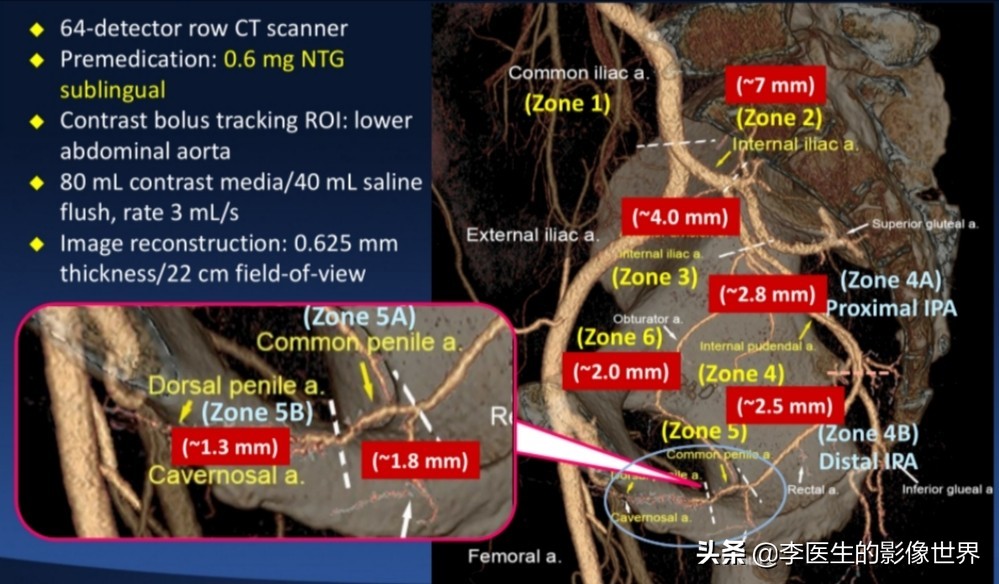

台湾王宗道相关研究

CT血管成像作为一种无创检查,能够作为数字血管造影(DSA)的有效补充,初步判断血管解剖结构异常、血管狭窄、外伤等。

为临床诊断、手术方案制定提供便利。以下为阴部内动脉CT血管成像MIP、VR图。仅供交流。